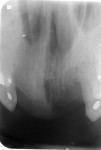

Sensory testing of the lip revealed profound left-sided V3 parasthesia. Radiographic examination showed sclerotic changes in the horizontal ramus of the left mandible. Serial panorex revealed rapid destruction with pathologic fractures appearing within a matter of 6 weeks (Figure 4 and Figure 5). A maxillofacial CT scan revealed extensive, progressive destruction and also revealed a pathologic fracture at the left angle of the mandible (Figure 6 through Figure 9).

The patient described was classified to be in Stage III (exposed/necrotic bone, pain/infection, pathologic fracture, extraoral fistula, osteolysis to inferior border) of BRONJ. Histology revealed acute osteomyelitis showing necrotic bone and acute inflammatory infiltrate and acute and chronic inflammation of the soft tissue (Figure 15 and Figure 16). Therefore, the plan was to do a surgical resection of the diseased bone with immediate reconstruction with a bone plate.

Postoperative panorex revealed reconstruction plate in place status post hemimandibulectomy (Figure 17). At 8 weeks post-surgical resection, the patient was doing well. She completed her 6 weeks of IV PenG and was put on an oral regimen of PenVK 500 mg every 6 hours for 6 months as per infectious disease protocol, and was maintained with chlorhexidine rinses three times daily.5 The patient was meticulously followed for evidence of new bony exposures, and two new exposures surfaced in the anterior and left maxillary regions (Figure 18 and Figure 19).